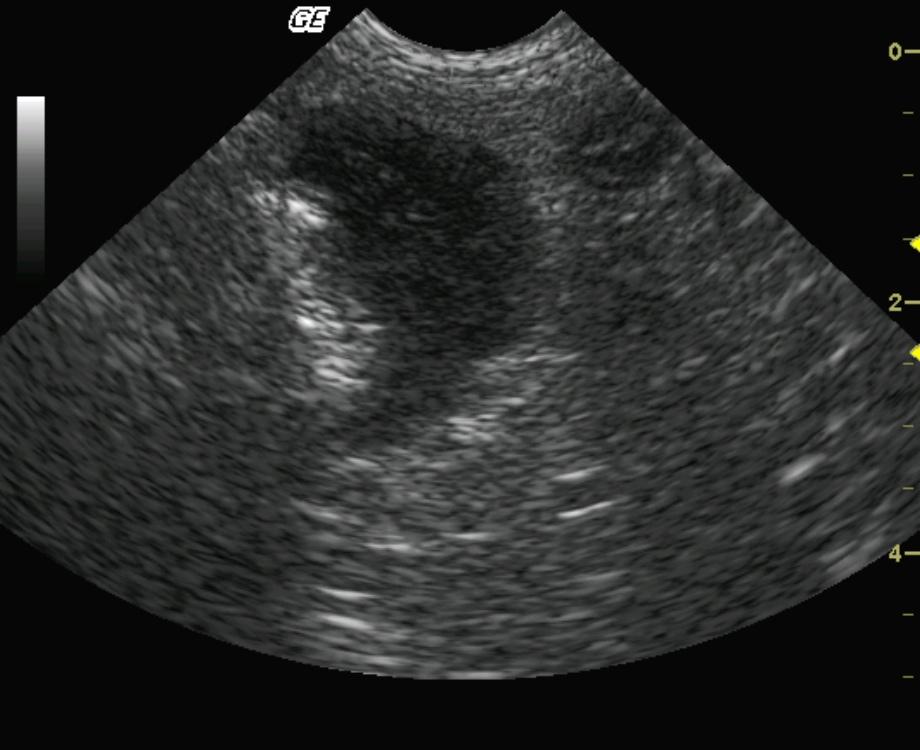

Marked, asymmetrical, focal bowel wall thickening is present. Transmural involvement is suspected; however, in certain regions the thickening appears to be involving and potentially arising from the muscularis layer. The peripheral borders of the mass are slightly lobulated; however, the serosal layer appears to be intact supporting encapsulation.

Intestinal neoplasia, complicated inflammatory lesion is less likely.